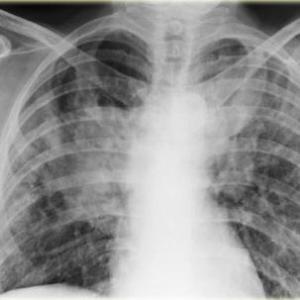

COVID-19 ups risk of pulmonary fibrosis

Infection with COVID-19 may increase the risk of pulmonary fibrosis, and patients with a severe disease are at greater risk of developing this complication, suggests a recent study.